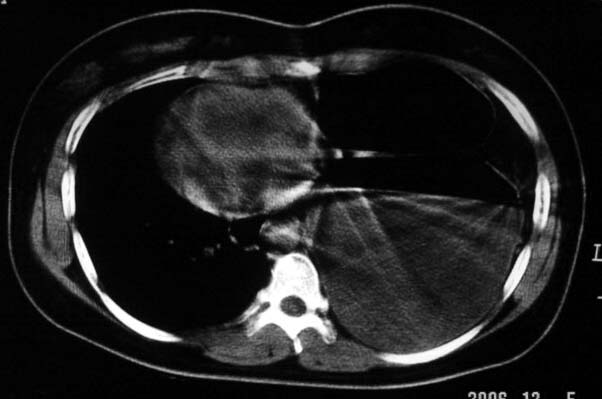

标题: CT5517:女性、24岁,反复胸痛、气促不能平卧半月。 [打印本页]

标题: CT5517:女性、24岁,反复胸痛、气促不能平卧半月。

左侧气液腔与胃腔影相连,考虑膈疝。钡餐检查有助于诊断。

我看这是膈疝,在纵隔窗第六\\七幅图像上可见胃粘膜影,再者可见两个腔影,这在液气胸是不会有的.

支持膈疝,纵隔窗内可见消化道的内容物。

左侧气液腔与胃腔影相连,考虑膈疝。口服urografin检查有助于诊断。

谨慎!喝钡透视一下吧。冒然报一液气胸,临床再穿刺引流结果把胃戳个大洞就麻烦了!